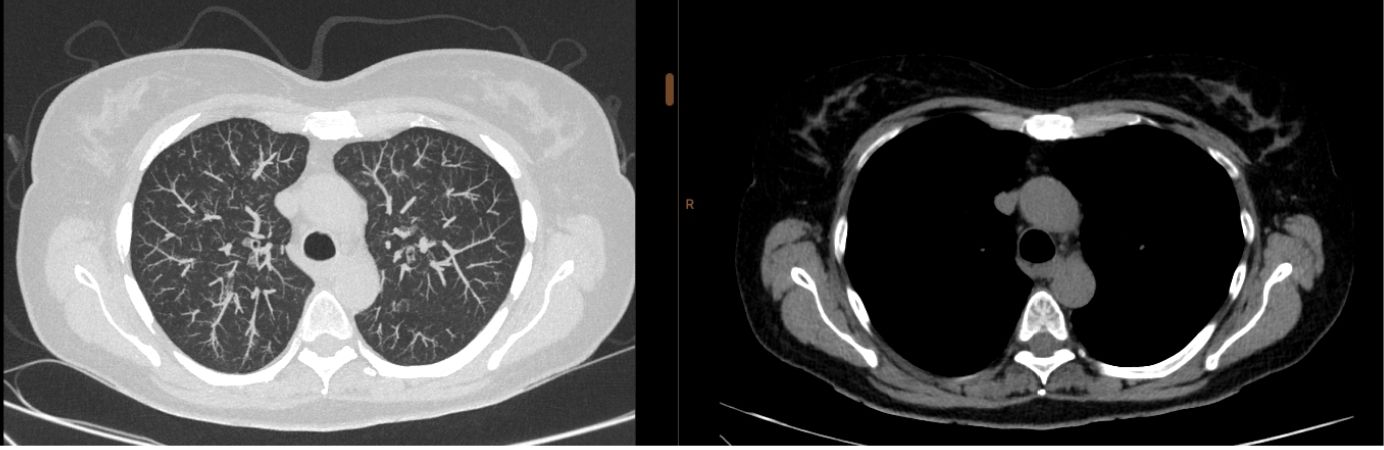

A TAC ao Tórax é um exame de imagiologia fundamental para o estudo dos pulmões, coração, vasos sanguíneos torácicos e estruturas do mediastino. É uma técnica de diagnóstico rápido, segura e altamente precisa, amplamente utilizada na investigação de doenças respiratórias, cardiovasculares e oncológicas

A TAC ao tórax é um exame de imagem que utiliza radiação ionizante para obter imagens detalhadas do pulmão, mediastino (local onde se encontram o coração, grandes vasos e linfonodos), parede torácica e outras estruturas do tórax. É um exame mais sensível e detalhado do que o raio X convencional.

A TAC ao Tórax é um exame que pode detetar várias alterações pulmonares e cardiovasculares, como por exemplo:

- Nódulos e tumores pulmonares;

- Pneumonias e outras infeções respiratórias;

- Doença pulmonar obstrutiva crónica (DPOC) e enfisema;

- Fibrose pulmonar e outras doenças pulmonares intersticiais;

- Derrame pleural e doenças da pleura;

- Tromboembolismo pulmonar e alterações da circulação pulmonar;

- Aneurismas ou dissecções da aorta torácica;

- Alterações mediastínicas, incluindo gânglios linfáticos aumentados;

- Entre outras.